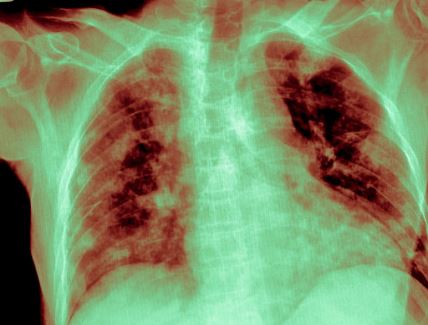

Rak pluća u Srbiji odnese 14 života dnevno: Rana dijagnoza je ključna za preživljavanje